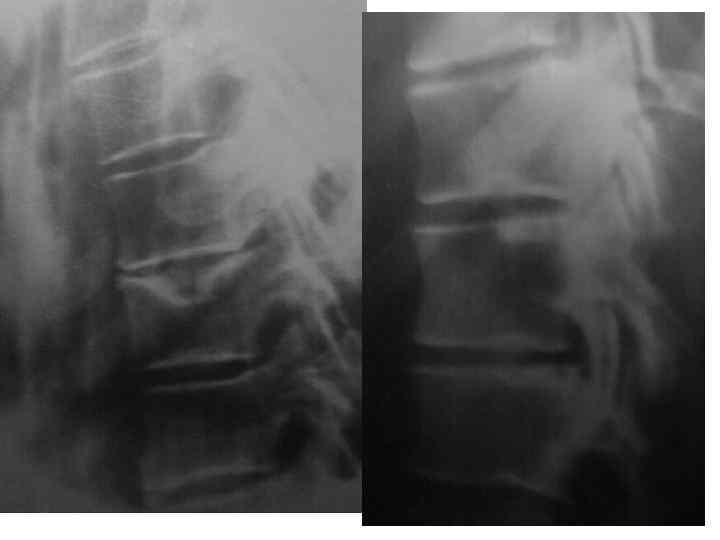

l l l На рентгенограмме шейного отдела позвоночного столба в боковой проекции определяется: выраженные распространенные дистрофические изменения в виде остеохондроза и артроза дугоотростчатых суставов: неравномерное сужение межпозвонковых пространств, субхондральный остеосклероз, костные разрастания по краям тел позвонков, сужение рентгеновских суставных щелей дугоотостчатых суставов с субхондральным остеосклерозом и небольшими костными разрастаниями по краям суставных поверхностей. Наиболее ярко эти изменения выражены в сегментах С 5 -6 -7 Признаки ограниченного смещения тел позвонков в виде симптома «распорки» и кифотической установки. Заключение: Остеохондроз шейного отдела позвоночного столба. Артроз дугоотростчатых суставов. Деформация шейного отдела позвоночника с нарушением статики.

l l l На рентгенограмме шейного отдела позвоночного столба в боковой проекции определяется: выраженные дистрофические изменения за счет остеохондроза - значительное, неравномерное сужение межпозвонковых пространств с нарушением их правильной клиновидной формы, выраженный субхондральный остеосклероз, значительные костные разрастания по передним краям тел позвонков. Наиболее ярко эти изменения представлены в сегментах С-5, 6, 7. Помимо этого, в этих же сегментах фиксируются дистрофические изменения дугоотростчатых суставов – сужение рентгеновских суставных щелей, субхондральный остеосклероз и костные разрастания по краям суставных поверхностей. Выпрямление физиологического лордоза. Признаки системного нарушения статики тел позвонков в виде симптомов кифотической установки. Деструктивных изменений нет Заключение: Комплекс дистрофических изменений шейного отдела позвоночного столба в виде остеохондроза и артроза дугоотростчатых суставов с преимущественными проявлениями в нижних сегментах отдела. Нарушение статики тел позвонков

l На рентгенограмме шейного отдела позвоночного столба в боковой проекции определяется: выраженные дистрофические изменения за счет остеохондроза с преимущественными проявлениями в сегменте С 5 -6 – сужение и деформация межпозвонковых пространств, выраженный субхондральный остеосклероз, значительные костные разрастания по краям тел позвонков. Выпрямление физиологического лордоза. Признаки нарушения положения тела С 4 (симптом «распорки» )

l На рентгенограммах шейного отдела позвоночного столба в двух проекциях определяется комплекс выраженных дистрофических изменений с преимущественными проявлениями в сегментах С 5 -6 -7 в виде остеохондроза и выраженного спондилоза за счет неравномерного сужения межпозвонковых пространств, субхондрального отсеосклероза и костных разрастаний как по краям тел позвонков с продолжением плоскости замыкательной площадки, так и под передней продольной связкой с образованием мощного костного соединения. Положение тел позвонков правильное, деструктивных изменений нет.